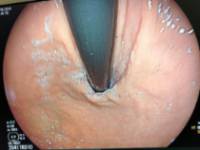

Imagen 2 –Post-procedimiento- : Misma visión del cardias en retroflexión, ya realizada la funduplicatura anterior, con mínimo sangrado, visualizando un agarre perfecto sobre el tubo del endoscopio)